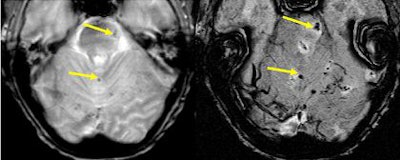

SWI offers a way to image the effects of stroke in terms of bleeding and changes in local oxygen saturation. Here, we show a case in which all other imaging methods failed to find the stroke. Very small amounts of iron can be detected with SWI. Bleeds otherwise totally invisible to conventional methods become visible with SWI.

| Left, conventional high resolution (TE = 40 msec) gradient-echo magnitude image shows nothing. Right, the SWI filtered phase image shows where the stroke took place. Image courtesy of E. Mark Haacke, Ph.D., Wayne State University, Detroit. |